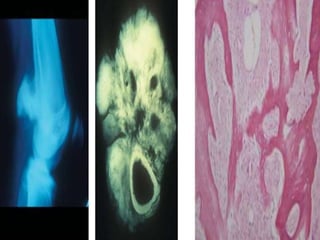

Parosteal

• 1-6%, arises from surface of long bones

• Medullary canal is spared

• Affects more females, slow growing

• Consists of a well differentiated fibrous stroma with

osseous components

• Bony trabeculae has a parallel Orientation and a

• "pulled steel wool pattern " on H and E